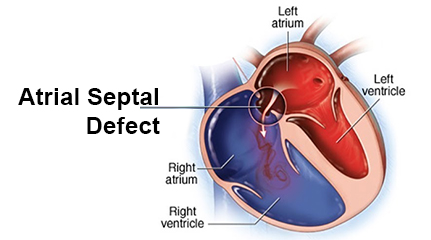

Overview

Package includes:

Days in hospital : 7 to 8 Day (For patient and one attendant)

Days in hotel : 14 Days (For patient and one attendant)

Room type in hospital : Shared

Room type in hotel : Private

Hotel category: Standard

Value added benefits of the ASD Surgical Closure Open Surgery:

Ø Doctor consultation charges

Ø Lab tests and diagnostic charges

Ø Room charges inside hospital during the procedure

Ø Surgeon Fee

Ø Nursing charges

Ø Hospital surgery suite charges

Ø Anesthesia charges

Ø Routine medicines and routine consumables (bandages, dressings etc.)

Ø Food and Beverages inside hospital stay for patient and one attendant.

Extra benefits:

ü Interpreter

ü Visa assistance

Ø Site tourism of the city

Ø Follow up with the doctor

Ø Airport pick up and drop

Ø Free online consultation with the doctor

Ø Priority appointments with the doctor

Ø Room upgrade from sharing to private

Overview

Package includes:

Days in hospital : 10 to 11 Days (For patient and one attendant)

Days in hotel : 14 Days (For patient and one attendant)

Room type in hospital : Shared

Room type in hotel : Private

Hotel category: Standard

Value added benefits of the ASD Closure:

Ø Doctor consultation charges

Ø Lab tests and diagnostic charges

Ø Room charges inside hospital during the procedure

Ø Surgeon Fee

Ø Nursing charges

Ø Hospital surgery suite charges

Ø Anesthesia charges

Ø Routine medicines and routine consumables (bandages, dressings etc.)

Ø Food and Beverages inside hospital stay for patient and one attendant.

Extra benefits:

ü Interpreter

ü Visa assistance

Ø Site tourism of the city

Ø Follow up with the doctor

Ø Airport pick up and drop

Ø Free online consultation with the doctor

Ø Priority appointments with the doctor

Ø Room upgrade from sharing to private